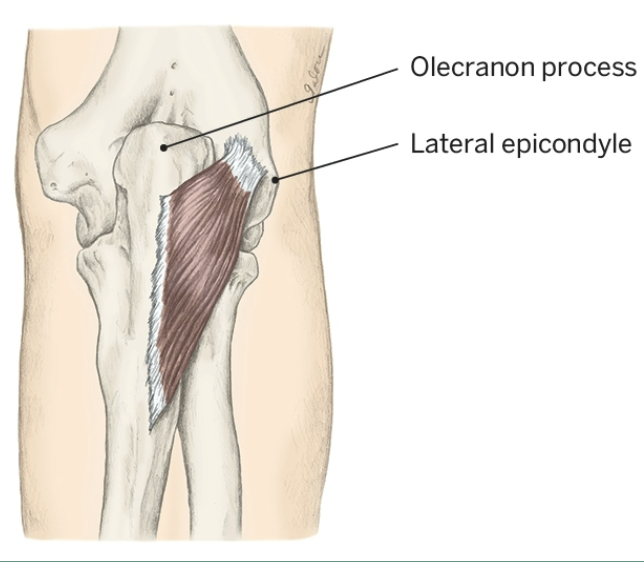

Action of Anconeus

Elbow Extension

Origin of Anconeus

Lateral epicondyle

Insertion of Anconeus

Olecronon process and posterior, proximal ulna

Nerve that the Anconeus innervates